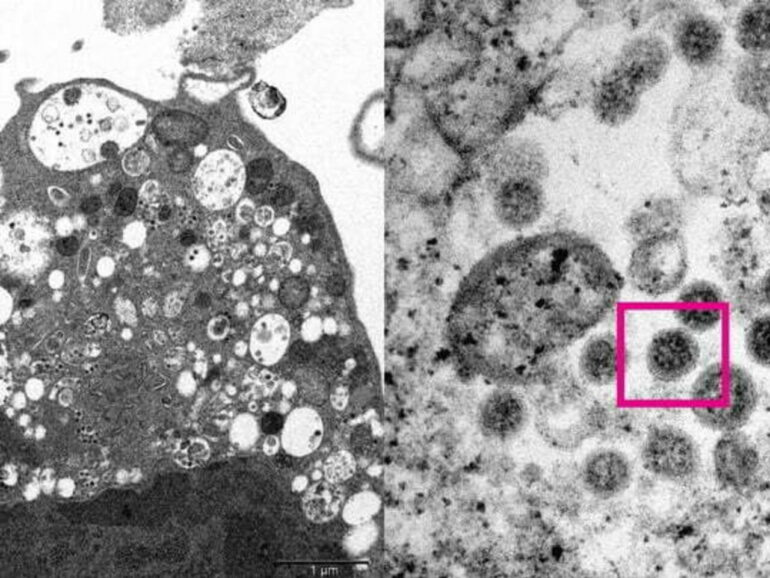

A subvariante BA.2 da ômicron, que rapidamente assumiu o controle na Dinamarca, é mais transmissível do que a mais comum BA.1 e mais capaz de infectar pessoas vacinadas, mostrou um estudo dinamarquês.

Em todo o mundo, a subvariante BA.1 “original” é responsável por mais de 98% dos casos de ômicron, mas sua prima próxima BA.2 rapidamente se tornou a cepa dominante na Dinamarca, destronando BA.1 na segunda semana de janeiro.

“Concluímos que a ômicron BA.2 é inerentemente substancialmente mais transmissível do que BA.1, e que também possui propriedades imunoevasivas que reduzem ainda mais o efeito protetor da vacinação contra infecções”, disseram os pesquisadores do estudo.